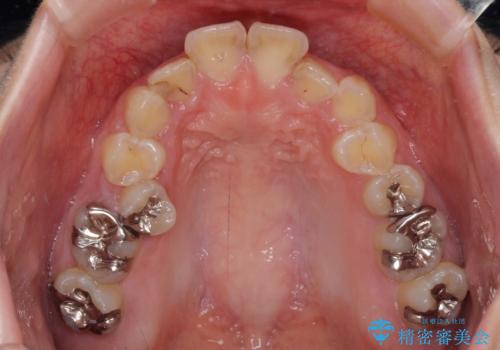

上下顎歯列ともに前方に突出していましたが、上顎歯列がより前方位にあったため、上顎左右は第1小臼歯を、下顎左右は第二小臼歯を抜歯することとしました。

下顎は過剰歯が埋伏しており、それが原因となってスペースが閉じなかったため、途中で抜歯して速やかに仕上げました。